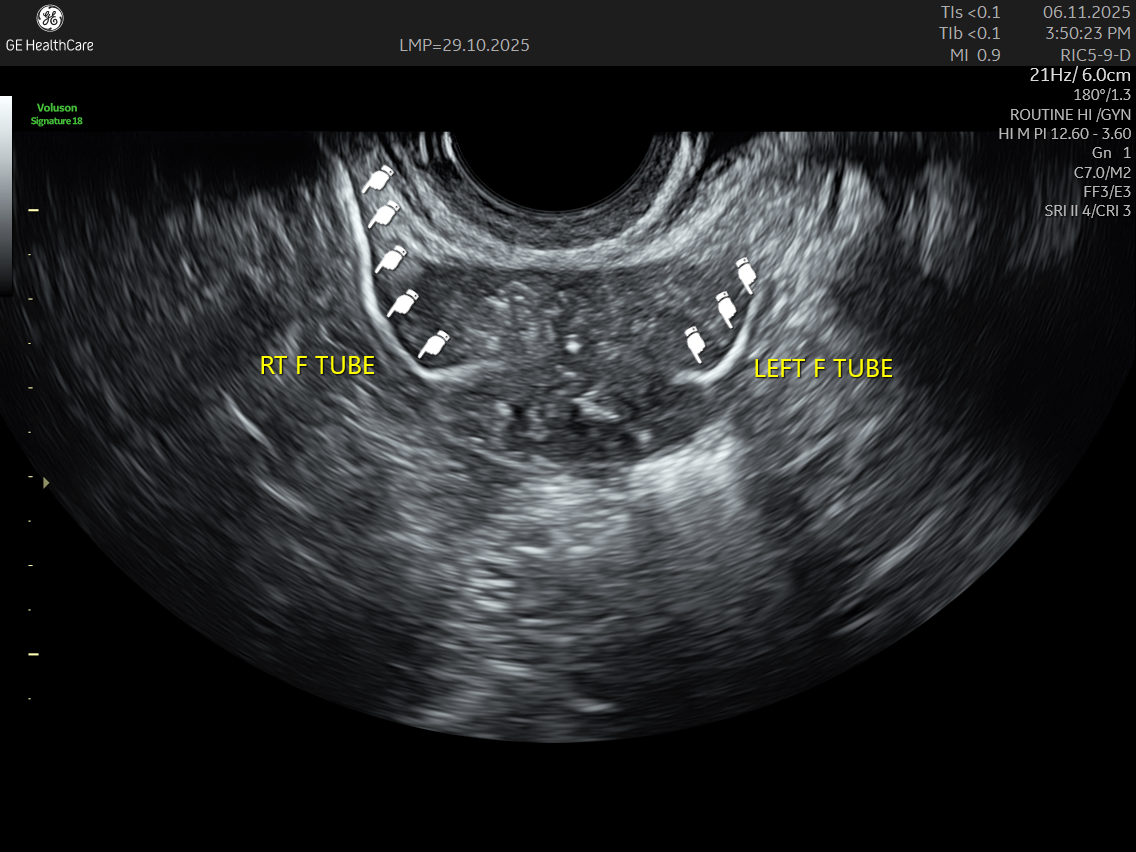

IMAGE GALLERY